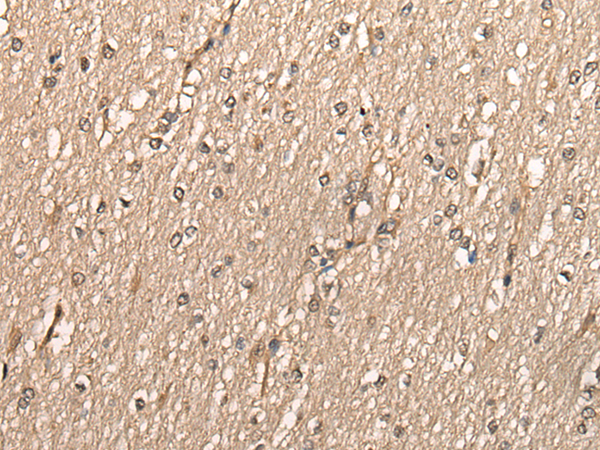

分类: 科研抗体货号: P06971别名: FETA, HPAFP应用: WB,IHC反应种属: Human